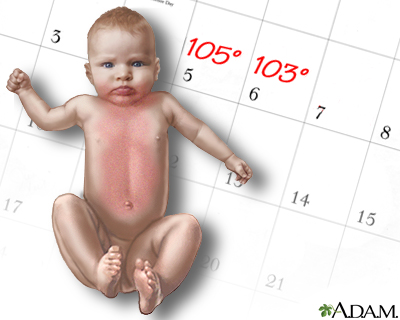

- Childhood illnesses such as chickenpox, measles, roseola, rubella, hand-foot-mouth disease, fifth disease, and scarlet fever.